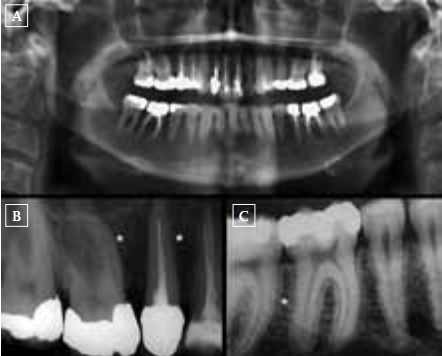

In March 2011, a previously healthy 50-year-old woman underwent an apicotomy (#36) and extraction of two elements (#15, 47) because of progressive mandibular bone resorption and radix fractures. Orthopantomogram (figure 1A) and dental X-ray (figures 1B and C) showed radiolucent spots and loss of the lamina dura, suggesting bone resorption and/or inflammation. Histopathological examination was consistent with undermining bone resorption, showing polynuclear osteoclast-like giant cells and mononuclear fibroblast-like cells, findings associated with either a giant cell granuloma or hyperparathyroidism. As endocrine work-up revealed a parathyroid hormone (PTH) serum level of 88.4 pmol/l (reference 0.6 to 6.7 pmol/l) and a normal calcium level of 2.46 mmol/l (reference 2.20 to 2.60 mmol/l, albumin 43 g/l), the patient was referred to the Outpatient Clinic of Endocrinology. Further analysis showed low 25-hydroxy-vitamin D (25-OHD) of 23 nmol/l (reference 75 to 250 nmol/l), elevated serum creatinine compared with a measurement in 2009 (122 and 74 mmol/l, respectively), and a normal phosphate level of 0.76 mmol/l.

Figure lA-C. (A) Patient's orthopantomogram with periapical bone loss at the first left lower molar (#36) and severe periodontal bone loss at the right lower molar region. (B) One of the patient's dental X-rays (right upper premolars and molars) showing loss of the lamina dura (white asterisk), if compared to the dental X-ray of a normal situation (figure 1C, white asterisk). Loss of lamina dura is a manifestation of hyperparathyroidism